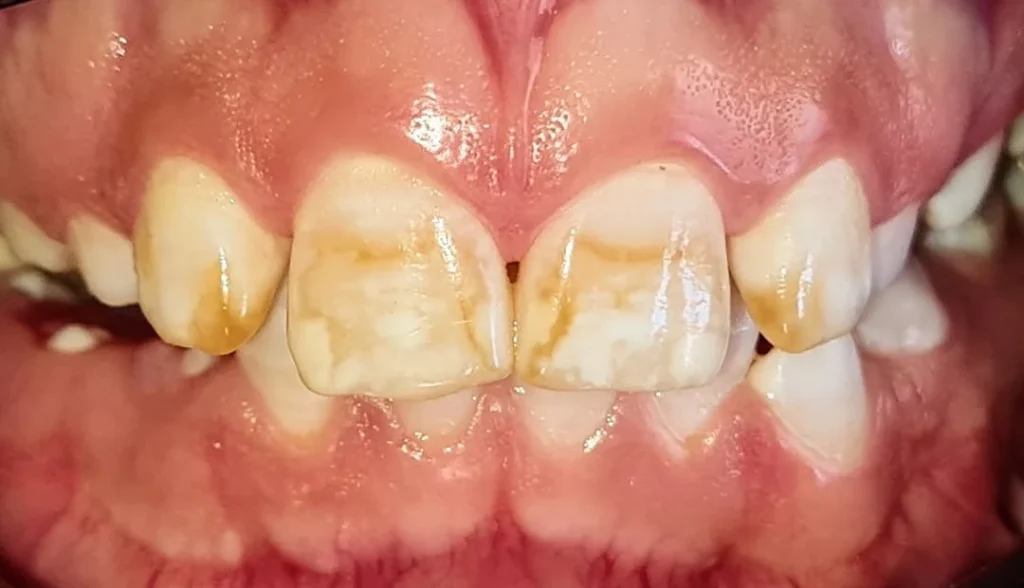

Casos más severos de fluorosis dental

Los casos severos de fluorosis dental presentan alteraciones significativas en el esmalte, que pueden incluir manchas marrones, áreas corroídas y una textura rugosa en la superficie de los dientes.

Este grado de fluorosis puede afectar no solo la apariencia, sino también la funcionalidad del diente.

La hipoplasia del esmalte y la hipomaduración pueden hacer que los dientes sean más vulnerables a la caries y otros problemas de salud dental.